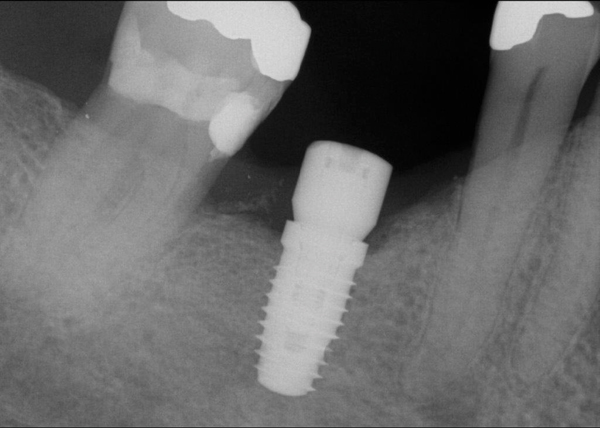

Fig 20. (Case 4) Radiograph of tooth No. 30, which had a hopeless prognosis.

Figure 20

Fig 21. Radiograph of extraction socket. Buccal plate was two-thirds resorbed.

Figure 21

Fig 22. Bone graft was placed in the socket and a d-PTFE barrier was used to cover the graft. The bone graft material was placed beyond the alveolar housing to accommodate shrinkage of graft material and to facilitate attaining a wide alveolar ridge. The barrier was removed after 5 weeks.

Figure 22

Fig 23. Implant inserted in a regenerated ridge after 6 months healing.

Figure 23

Fig 24. Cone beam scan demonstrating bone circumferentially around the dental implant.

Figure 24

Fig 25. Radiograph showing appearance of restored implant after 1 year.

Figure 25